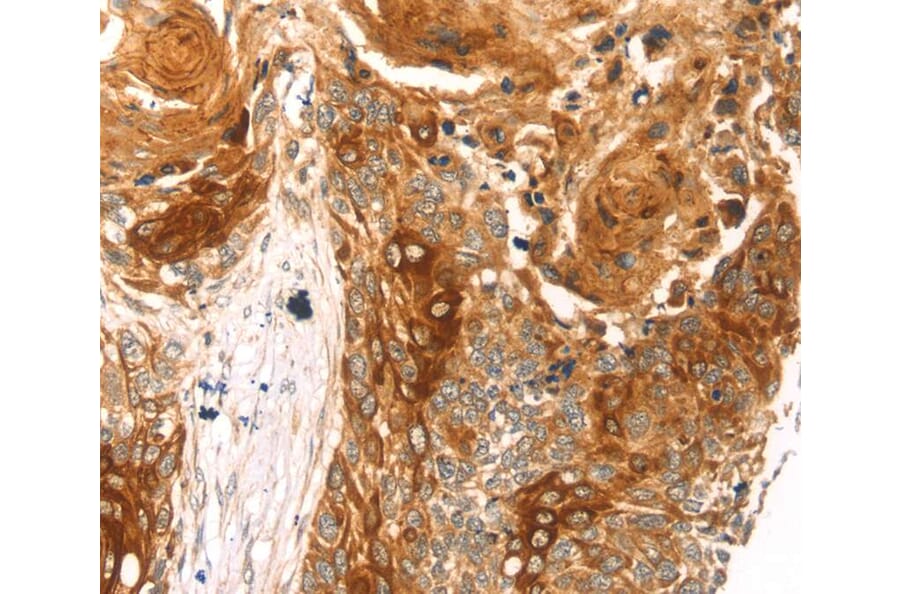

Immunohistochemistry - Anti-THAP9 Antibody (A46348)

Immunohistochemical analysis of paraffin-embedded Human oesophagus cancer tissue using #40243 at dilution 1/20.